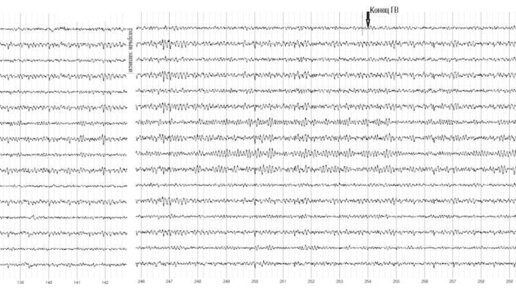

В о время рутинного ЭЭГ-обследования в соответствии с «Рекомендации экспертного совета по нейрофизиологии Российской противоэпилептической лиги по проведению рутинной ЭЭГ» проводят ряд активирующих или функциональных проб. В ходе этих проб определяют функциональное состояние головного мозга в различных состояниях. К таким пробам относят фоновую запись, открывание глаз, закрывание глаз, фотостимуляцию и другие. В данном материале подробно рассматривается функциональная проба Гипервентиляция (проба с глубоким дыханием)...